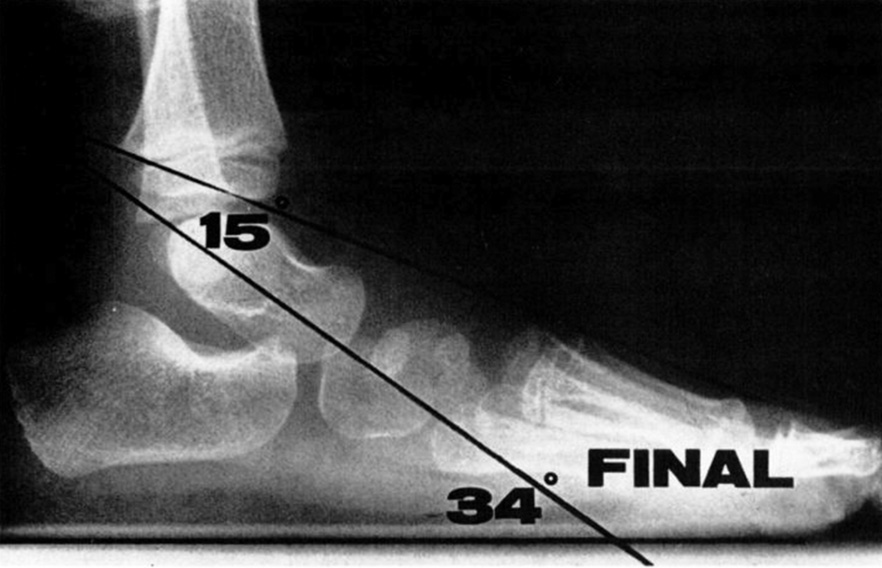

Выраженность плоскостопия, определенная с помощью рентгенографии у детей лечебных групп в начале и в конце исследования, представлены на рис. 5–7.

Рис. 8. Рентгенография стопы (того же пациента, что и на рис. 3 и 4) в положении стоя без коррекционной обуви по истечении трех лет лечения. Боковая проекция: таранно-подошвенный угол уменьшился до 34°, а угол между таранной и I плюсневой костями — до 15°